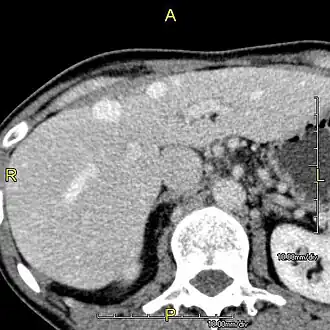

-

Axial CT image showing anomalous hepatic veins coursing on the liver's subcapsular anterior surface[74] -

Maximum intensity projection (MIP) CT image as viewed anteriorly showing the anomalous hepatic veins coursing on the anterior surface of the liver -